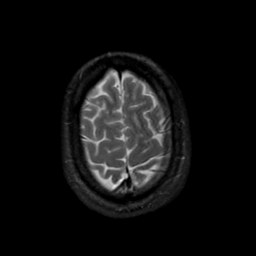

MR Study #19, August 25, 1991 -- Slice #43

[Home][Help][Clinical][Tour 1][Tour 2] Slice 43